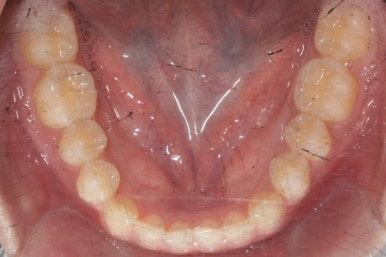

이번 환자분의 경우는 아랫니는 약간 삐뚤함이 있지만 굳이 교정치료를 원하지 않으셨기 때문에 윗니들만 부분교정으로 해결하기로 했습니다.

이상적으로라면 위-아래를 한 쌍으로 해야 교합을 맞추기에 유리하지만 이번의 경우는 윗니만 해도 충분히 교합을 맞출 수 있겠다고 판단하여 부분교정을 하였습니다.

윗니만 하고 싶다고 무조건 윗니 부분교정이 가능한 것이 아니기 때문에 반드시 교정전문의와의 상의를 추천드립니다.

아래치아는 여전히, 당연히 장치가 붙지 않은 채로 그대로 둡니다.

마무리 때의 사진입니다.

윗니만 부분교정하였지만 교합에도 이상 없이 매복되었던 송곳니는 매우 잘 위치를 잡았습니다.

썩은 유치 대신 영구치 송곳니는 매우 자연스럽게 위치되었습니다. 아랫니는 교정하지 않았기 때문에 약간 삐뚠 느낌은 남아있지만 맞물림은 크게 문제가 없게 마무리 되었습니다.